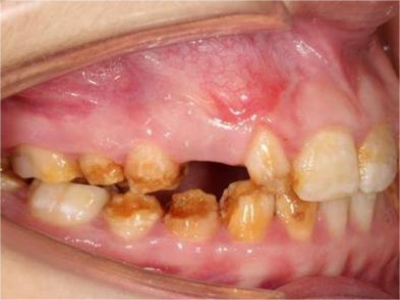

牙釉质发育不全牙表面上有坑图

牙釉质发育不全发展到严重时,导致牙釉质表面缺损,表现为带状、窝状的褐色凹坑,容易积存食物残渣诱发龋齿,表现为牙齿边上出现深褐色小洞。

牙釉质发育不全牙齿上有褐色坑图

牙釉质发育不全的患者随着疾病逐渐发展,除了出现牙齿表面发白、不通透外,还可有褐色的条状、窝状凹陷,继之出现数条并列的凹陷。

牙釉质发育不全牙齿上棕色的坑图

牙釉质发育不全程度严重时,牙齿上出现较深的条状、点状凹陷,内含深褐色物质,并且牙齿尖端的牙釉质缺失,牙齿变得相对脆弱。

牙釉质发育不全牙齿棕色有缺损图

牙釉质发育不全患者牙齿出现明显的缺损表现,并于表面形成深褐色的蜂窝状、竖条状的凹坑,甚至形成洞,患者上下牙失去咬合能力。

牙釉质发育不全牙齿表面棕色有坑图

牙釉质发育不全导致牙釉质表面呈棕褐色,有带状、窝沟状凹陷,以及黑点,牙釉质大面积缺损,牙齿表面变得粗糙,可出现进食时敏感等不适。

牙釉质发育不全牙面上棕色小坑图

重度牙釉质发育不全患者牙面出现带状或蜂窝状棕色小坑,累及多个牙齿,无明确的分布规律,严重影响牙齿美观,建议通过牙齿修复治疗恢复牙齿外观。

牙釉质发育不全牙齿缺损有小坑图

重度牙釉质发育不全导致牙釉质表面呈棕褐色、棕黄色,其上有条状、窝状凹陷,并出现牙齿缺损,导致咬合关系破坏,也会出现对刺激敏感、疼痛等自觉症状。

牙釉质发育不全牙齿缺损图

牙釉质发育不全磨牙后,牙齿表面的牙冠快磨没了,出现牙齿缺损现象,露出牙髓,缺损面粗糙不平,同时存在牙龈肿胀、牙齿松动或移位等现象,肉眼可见缺损面颜色发黄或发黑。